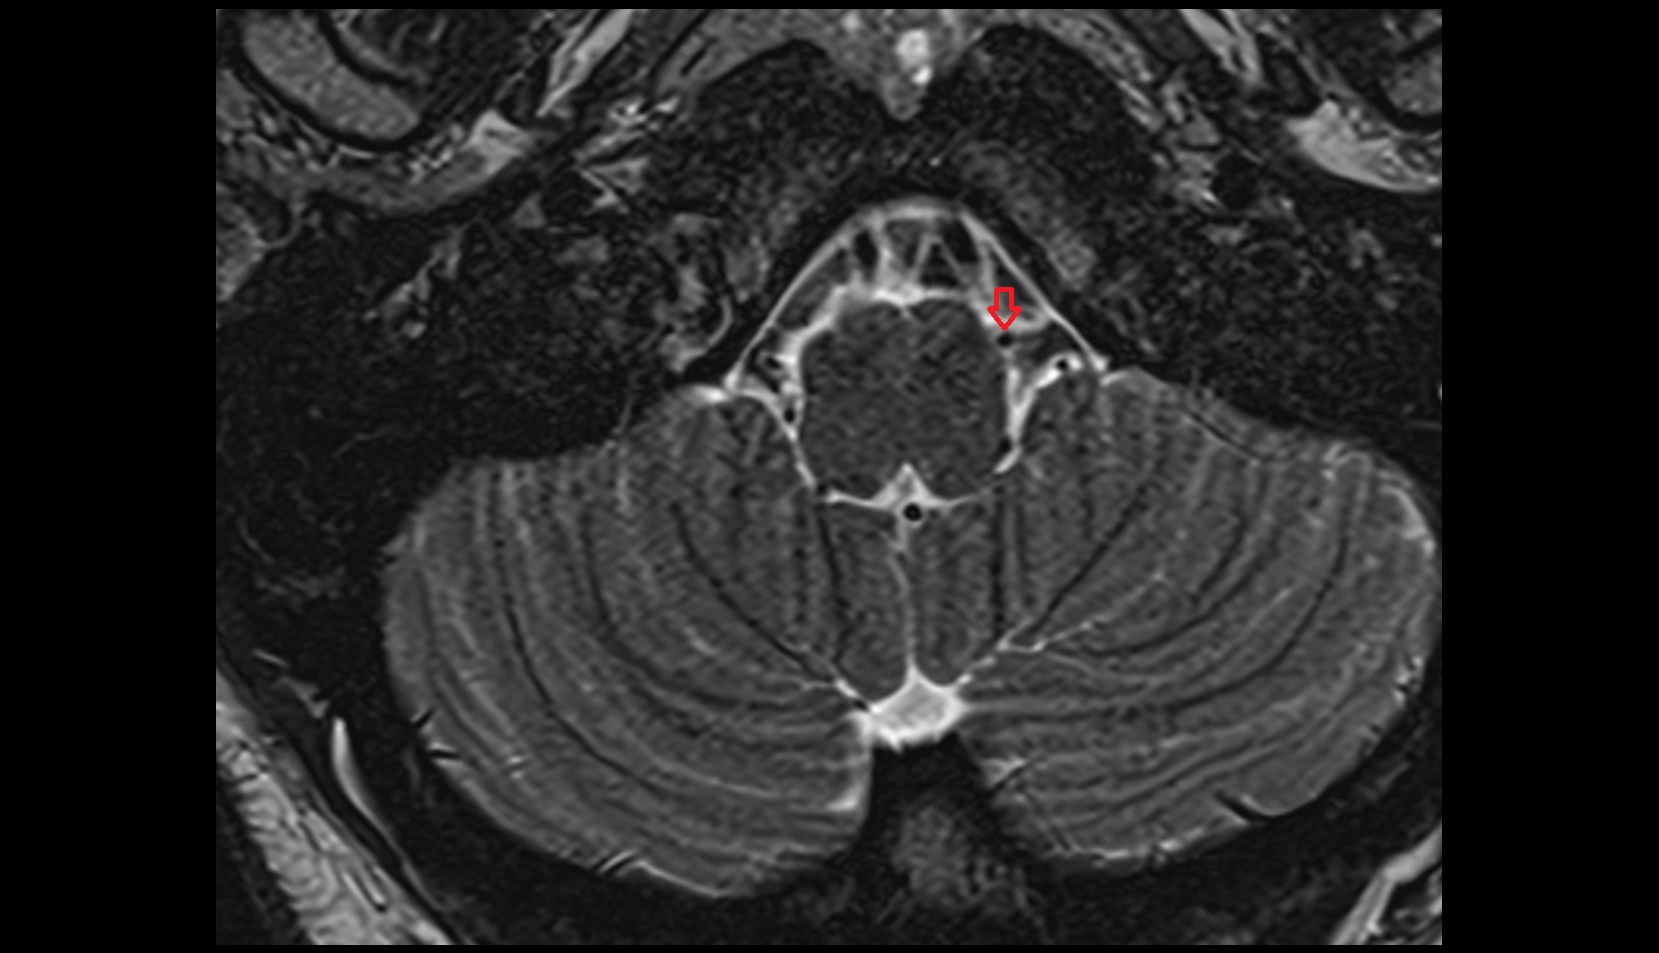

- Traversing nerve root of spinal nerve

- Exiting nerve root of spinal nerve